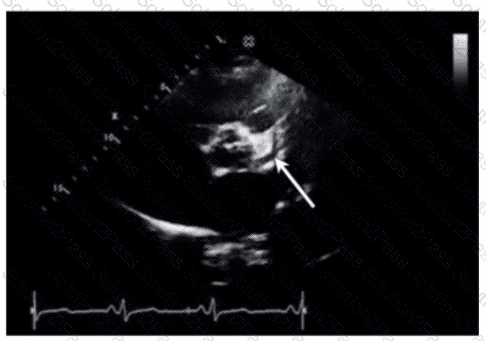

Which finding is demonstrated in this video?

Which coronary artery is identified by the arrow on this image?